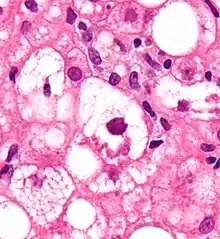

Les corps de Mallory entrent le plus souvent dans le cadre d'une hépatopathie alcoolique[1]. Ils représentent des amas résiduels de microfilaments consécutifs à la toxicité de l’alcool et de ses métabolites.

De manière plus générale, les corps de Mallory se retrouvent aussi dans une stéatohépatite non alcoolique[2]